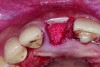

In cases with an incomplete facial plate, the ice cone technique was recommended.20 In this method, a collagen membrane was trimmed to the shape of an ice cone and placed into the socket against the inner aspect of the facial bone. The socket was filled with bone substitutes, and the coronal portion of the membrane was used to cover and protect the underlying bone substitutes. A non-resorbable PTFE membrane can be used for site preservation as well.21 This membrane, if secured to bone, can be left exposed, and epithelialization will occur over it. It was found that sockets grafted with a mineralized bone allograft and PTFE membrane had 47.4% new bone formation and 14.7% residual graft particles. In addition, there was minimum resorption of the buccal bone thickness, as indicated by a 0.3-mm horizontal bone resorption and a 0.25-mm vertical bone resorption.22 A recent systematic review reported that the use of PTFE membranes in ridge preservation shows potential in maintaining ridge dimensions23 and possibly aiding in increasing the zone of keratinized mucosa. Therefore, the use of PTFE membrane may be preferred in ridge preservation of sites in the esthetic zone. Figure 1 and Figure 2 illustrate the use of PTFE membrane in ridge preservation for implant replacement in the esthetic zone. Other authors have also attempted primary closure of the socket or to improve the ridge topography with soft-tissue grafts, but it has not been proven to be effective in increasing bone regeneration.18

Placement of PTFE membrane to form the missing buccal bone. - See more at: http://cdeworld.com/courses/4756-Site_Preparation_for_Implant_Replacement_in_the_Esthetic_Zone#sthash.O5zxOUde.dpuf

Figure 1